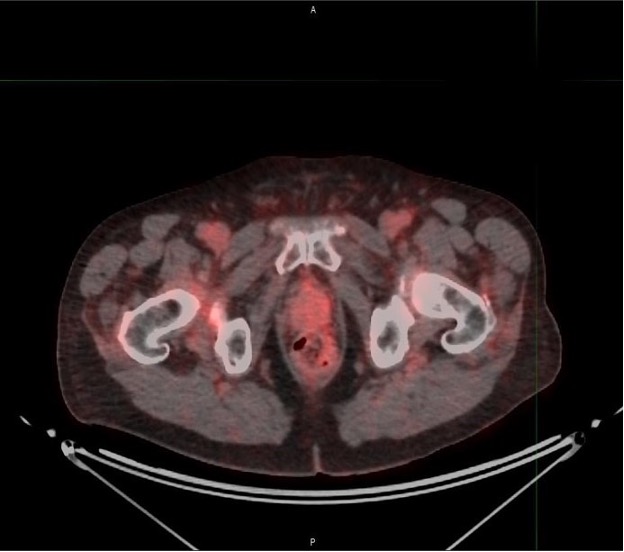

Is PSMA PET/CT More Beneficial than Bone Scintigraphy in Detecting

PSMA-PET is rapidly changing the standard of care for prostate

Sequencing of Conventional and PSMA-PET Imaging in Prostate Cancer